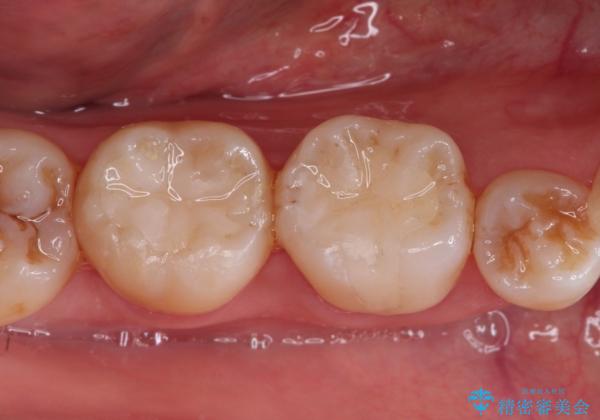

メタルインレーからセラミックインレーへ

セラミックインレーに治療を行っております。

e-max プレスインレーにて修復治療を行っているため適合性及び審美性の高い治療を行うことができます